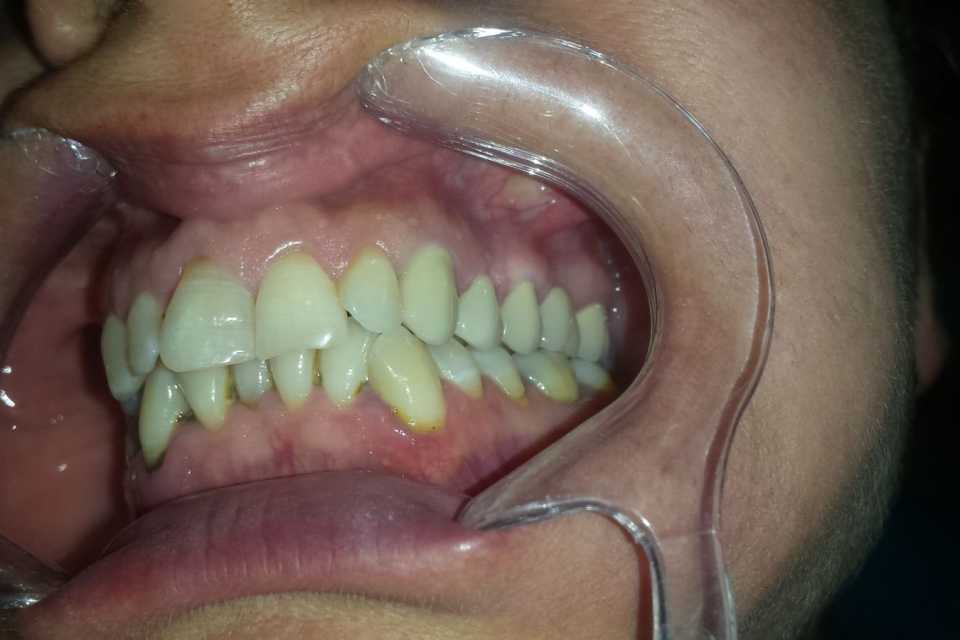

Pacienta s-a prezentat în cabinet din motive estetice și funcționale, acuzând sângerări gingivale și un miros neplacut. Am îndepărtat vechea lucrare, am refăcut tratamentele de canal, bonturile protetice și am slefuit bonturile cu prag.